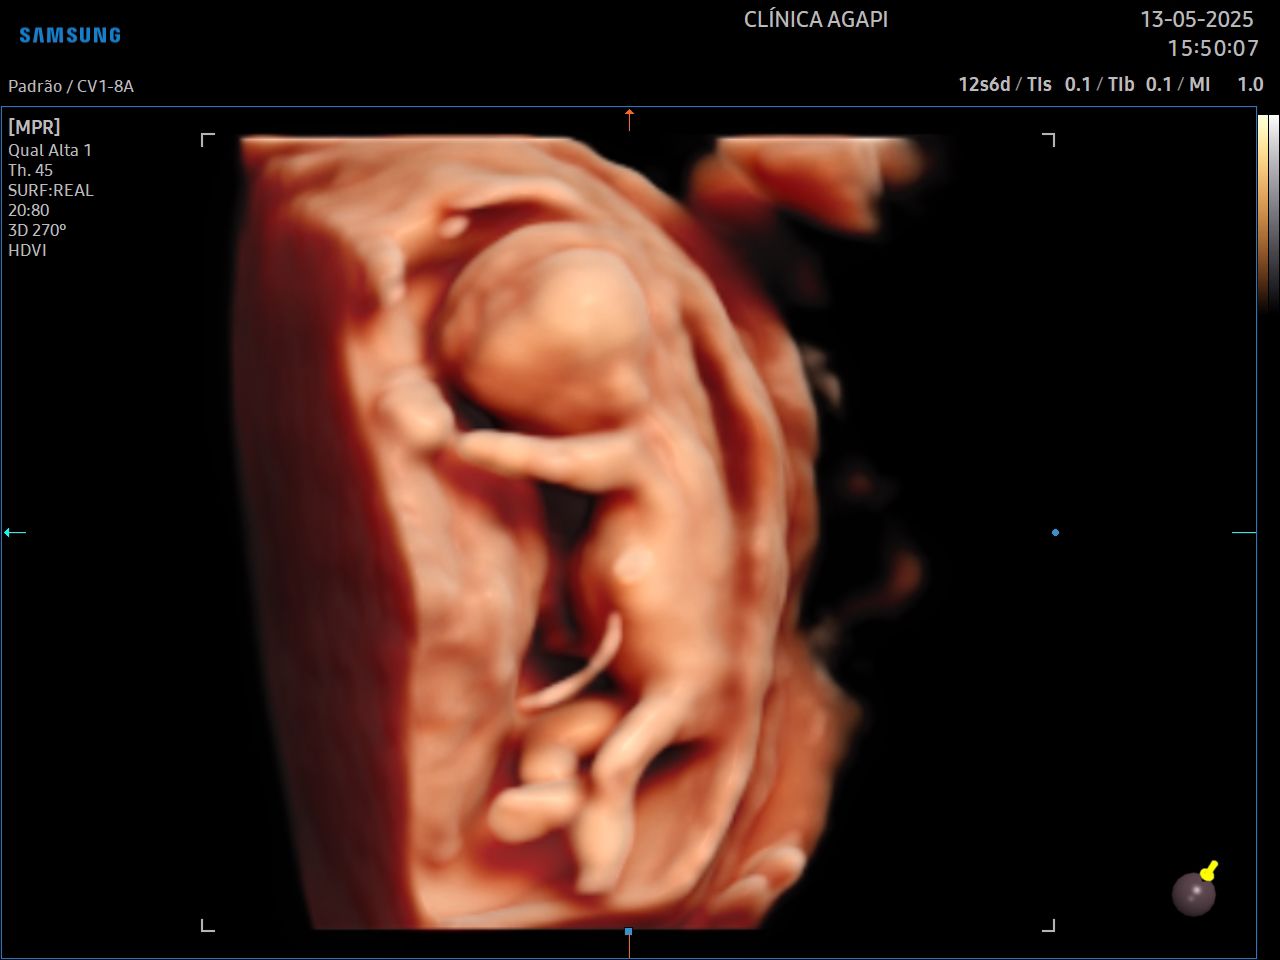

O 3D é realizado com um transdutor especial que reconstrói a superfície adquirida em uma imagem de 3 dimensões, estática. Já o 4D permite visualizar essas imagens com movimento do bebê em tempo real. Com a tecnologia HD live temos a cor do feto que dá a impressão da cor da pele.

A capacidade de aquisição de uma boa imagem tridimensional (3D/4D) depende de vários fatores, dentre eles: quantidade de líquido amniótico, posição fetal, inserção placentária, espessura do tecido celular subcutâneo materno, número de fetos, padrão de movimentação fetal durante o exame, dentre outros fatores que devem sempre ser individualizados.

Aqui na AGAPI, em qualquer exame - e se o bebê colaborar, sempre vamos fazer esses registros incríveis que a mamãe tanto ama.